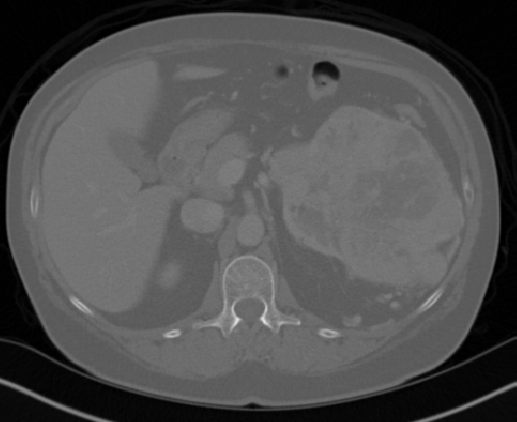

We argue that the sub-optimal paradigm of processing different abstractions within a single CNN pipeline can be remedied through the effective processing of information in a structured manner. Consequently, we devise strategies for disentangling the edge and texture information within a single training pipeline. Figure 2 illustrates how our proposed module, dubbed EG-CNN, can be paired with any existing CNN encoder-decoder to improve segmentation quality near intensity edges. We have applied our EG-CNN to the tasks of brain and liver tumor segmentation in medical images (Figure 3).

(1) Brain MR (2) Liver MR (3) Liver CT (4) Lung CT